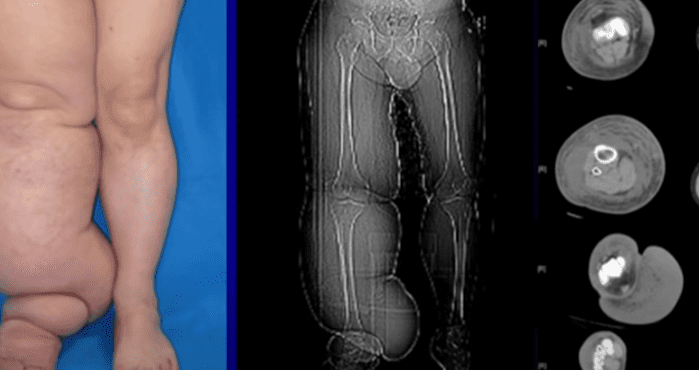

한 남성의 성기 크기가 60kg가 되어버렸다고 한다.

사연의 주인공은 라스베거스에 거주하고 있는 웨슬리 워렌 주니어인데 60kg정도의 거대한 음낭을 달고 살고 있다고 한다.

또 음경이 음낭 안으로 파묻혀서 성생활은 불가능했고 소변을 보거나 걷는 것조차도 불편하다고 한다.

그가 앓고 있던 성기가 비대해진 질병, 그의 병명은 상피병이었다.

원인은 많은데 그 중에서도 모기 때문에 발생하는 경우가 주로 많으며 모기가 매개한 기생충이 원인이다.

상피병은 그 증세가 나타나기 전에 림프 부종이란 병을 먼저 거친다. 몸이 붓는 부종을 오래 방치하면 상피병 단계로 넘어간다.

피부 조직이 섬유화되면서 굳기 시작하고 한번 섬유화가 진행된 조직은 원래대로 복구할 방법이 없다.